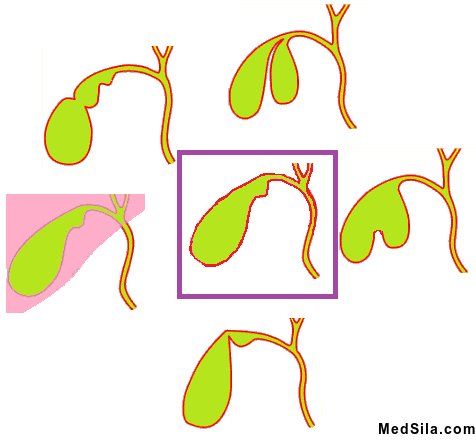

- Различные аномалии строения желчного пузыря или желчевыводящих протоков: перетяжки, перегибы, мешающие нормальному оттоку желчи;